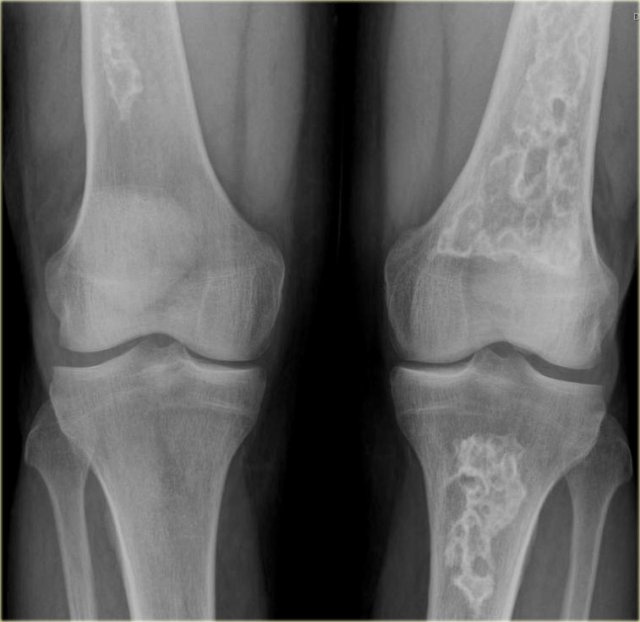

On the left more examples of GCT around the knee.

Notice that most of these lesions are well-defined and located in the epiphysis and extend into the metaphysis.

Some extend onto the articular surface (yellow arrow and small red arrows).

The lesion on the upper right has an ill-defined border with a broad zone of transition (blue arrow).